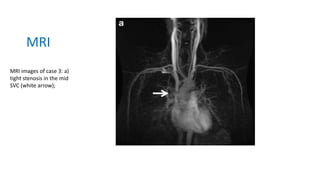

MRI images of case 3: a)

tight stenosis in the mid

SVC (white arrow);